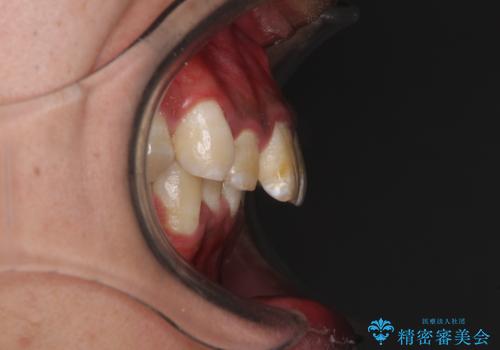

深い咬み合わせと前歯のデコボコ ワイヤー装置での抜歯矯正

- 深い咬み合わせと前歯のデコボコを改善したいとのことで来院された患者様です。

口元の突出感はないものの、上顎前歯のデコボコが著しく、右側の咬み合わせがずれていたため、上顎右側第一小臼歯1本を抜歯することとしました。

咬合力が非常に強く、抜歯したスペースがなかなか閉じないであろうことは予想できましたが、思っていた以上に期間がかかりました。

前歯のすり減りも著しかったため、仕上げの位置の調整にも期間を要しました。